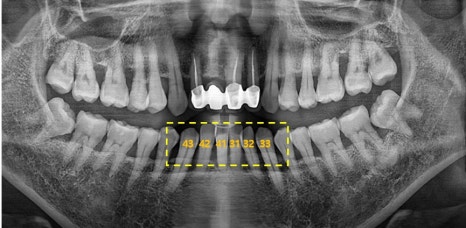

▲ 초진 파노라마

노란색으로 표시 된 선을 보시면 치주가 좋지 않아 전체적으로 잇몸이 내려 앉았지만

특히 앞니 부분에 잇몸이 많이 패여 있는것을 보실 수 있습니다.

# 42 41 #31 32 치아는 흔들림이 심해 발치 후 임플란트 치료와 #42 41 치아쪽에는

뼈이식도 함께 진행 하였습니다.

#43 33 치아는 신경치료 이후 크라운치료로 마무리 하였습니다.